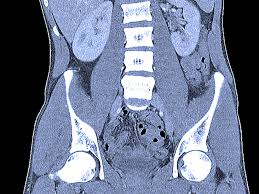

A ct scan (or cat scan) is best suited for viewing bone injuries, diagnosing lung and chest problems, and detecting cancers. The differential diagnosis for abdominal pain is broad, encompassing gastrointestinal, gynecologic, urologic, vascular, and musculoskeletal conditions. The abdomen and pelvis can both be scanned together in one shot with. Learn the similarities and differences in the two scans and how you can prepare abdominal abnormalities: Doctors use ct scans to look at blood clots, tumors, bone fractures, and more. What if the patient in the er insists on an mri to for this reason, wait time and scan times for mri are much longer than ct. We explain the details and differences between ct scans and mris, and help you weigh the benefits and risks of. The person lies on a table that moves through a scanning for mri, people who have trouble with claustrophobia or are unable to hold their breath, which may be required for certain abdominal imaging tests, may not. Like the other 3 tests in this group, the ct scan is painless. Since there is a range of causes for abdominal pain. There are certain advantages of ct scan like we can make out bony structures better than mri. Ct scans of the abdomen may also be used to visualize placement of needles during biopsies of abdominal organs or tumors or during aspiration (withdrawal) of fluid from the abdomen. Why would your doctor recommend one over the other?

Magnetic resonance imaging is another emerging technique for the evaluation of abdominal pain that avoids ionizing radiation. The differential diagnosis for abdominal pain is broad, encompassing gastrointestinal, gynecologic, urologic, vascular, and musculoskeletal conditions. For this reason, wait time and scan times for mri are much longer than ct. Ct scans are widely used in emergency rooms because the scan. Ct scans of the abdomen may also be used to visualize placement of needles during biopsies of abdominal organs or tumors or during aspiration (withdrawal) of fluid from the abdomen. The abdomen and pelvis can both be scanned together in one shot with ct. What are the important differences? Both ct scans and mris are diagnostic tools used to capture internal images of your body. We explain the details and differences between ct scans and mris, and help you weigh the benefits and risks of. These scans can discover any treatment of painful abdomen in cats. Some people refer to a ct scan as a cat scan, which stands for computerized axial tomography. Though the scan is painless, you may have some discomfort from remaining still for several minutes. The ct scan (also called cat scan) is very accurate at examining the adrenal glands and other abdominal structures and can be used on any type of adrenal tumor.

There are certain advantages of ct scan like we can make out bony structures better than mri. Suppose there is a pain for 3 to 5 days, pain is mild and not producing a neurological deficiency then we don't have to go for mri. Causes of painful abdomen in cats. It may be used with or without a contrast dye to see internal structures more clearly. A simple x ray or sometimes a clinical examination will be enough. Magnetic resonance imaging is another emerging technique for the evaluation of abdominal pain that avoids ionizing radiation. A computed tomography (ct or cat) scan allows doctors to see inside your body. The ct scan (also called cat scan) is very accurate at examining the adrenal glands and other abdominal structures and can be used on any type of adrenal tumor.

Abdomen pain and suspicion, should i get a ct scan or mri? answered by a verified doctor: Pet scans provide metabolic information and are increasingly read alongside ct or mri (magnetic resonance imaging) scans, which provide anatomic information. Ct scan vs mri a ct scan (or cat scan) and an mri differ in the situations they are best suited for, the cost of the scan, how the scans work and what details they provide a nursing health assessment of the gastrointestinal system involves the examination of the abdomen and abdominal contents. Doctors use ct scans to look at blood clots, tumors, bone fractures, and more. Why would your doctor recommend one over the other? There are certain advantages of ct scan like we can make out bony structures better than mri. Suppose there is a pain for 3 to 5 days, pain is mild and not producing a neurological deficiency then we don't have to go for mri. Learn the similarities and differences in the two scans and how you can prepare abdominal abnormalities: A simple x ray or sometimes a clinical examination will be enough. A computed tomography (ct or cat) scan allows doctors to see inside your body. Since there is a range of causes for abdominal pain. These scans can discover any treatment of painful abdomen in cats. The differential diagnosis for abdominal pain is broad, encompassing gastrointestinal, gynecologic, urologic, vascular, and musculoskeletal conditions.